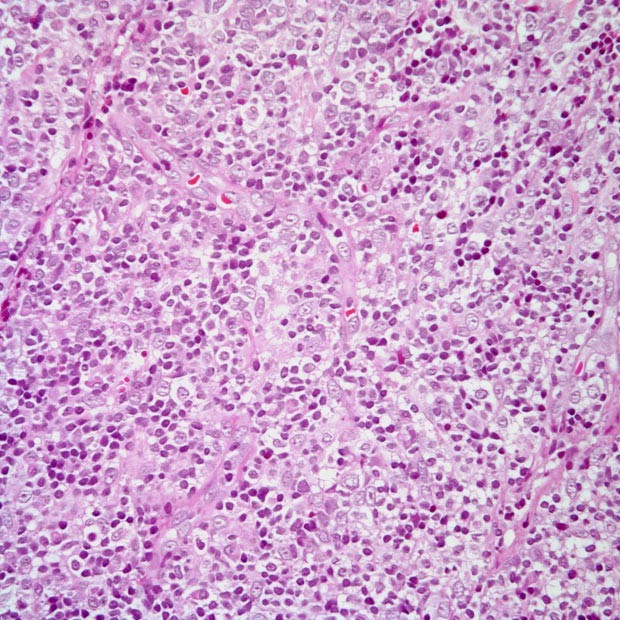

多图│教您识别慢性淋巴细胞白血病

620x620 - 158KB - JPEG